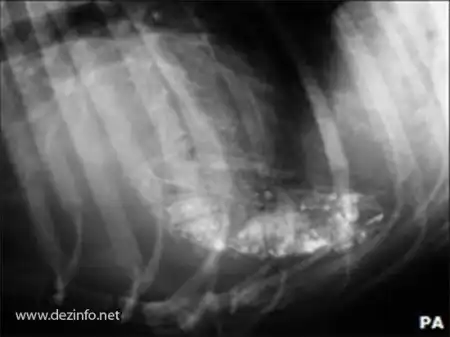

130 обрезанных ногтя нашли в желудке у Рокси.